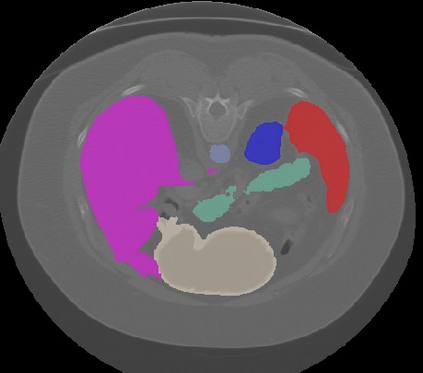

Transformers, the default model of choices in natural language processing, have drawn scant attention from the medical imaging community. Given the ability to exploit long-term dependencies, transformers are promising to help atypical convolutional neural networks (convnets) to overcome its inherent shortcomings of spatial inductive bias. However, most of recently proposed transformer-based segmentation approaches simply treated transformers as assisted modules to help encode global context into convolutional representations without investigating how to optimally combine self-attention (i.e., the core of transformers) with convolution. To address this issue, in this paper, we introduce nnFormer (i.e., Not-aNother transFormer), a powerful segmentation model with an interleaved architecture based on empirical combination of self-attention and convolution. In practice, nnFormer learns volumetric representations from 3D local volumes. Compared to the naive voxel-level self-attention implementation, such volume-based operations help to reduce the computational complexity by approximate 98% and 99.5% on Synapse and ACDC datasets, respectively. In comparison to prior-art network configurations, nnFormer achieves tremendous improvements over previous transformer-based methods on two commonly used datasets Synapse and ACDC. For instance, nnFormer outperforms Swin-UNet by over 7 percents on Synapse. Even when compared to nnUNet, currently the best performing fully-convolutional medical segmentation network, nnFormer still provides slightly better performance on Synapse and ACDC.